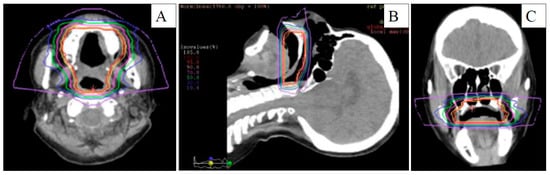

2. Case Report